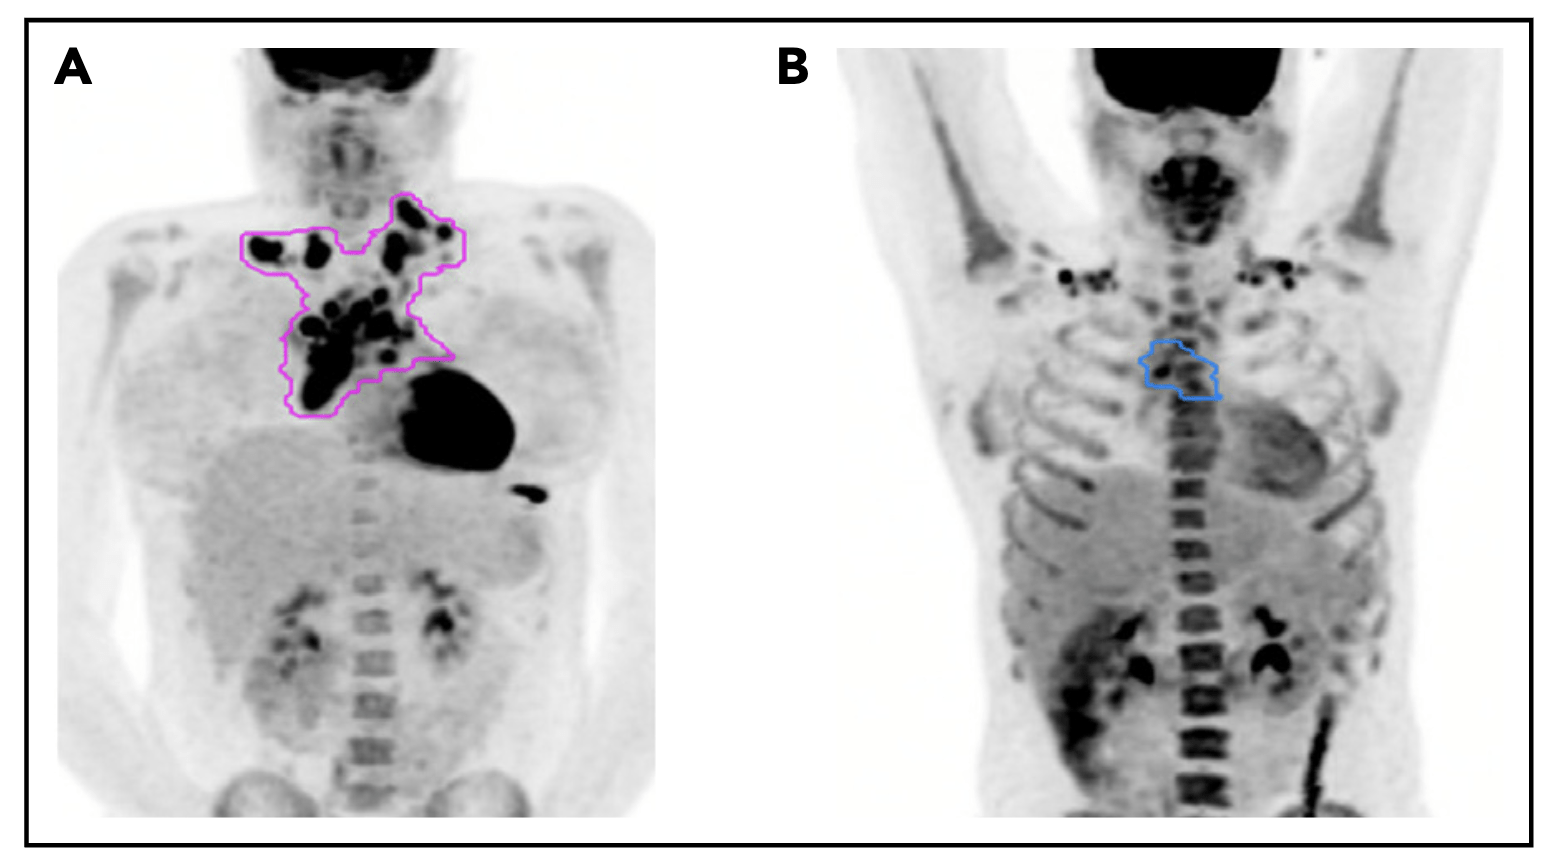

Pattern of relapse definitions. (A) Theoretical outline (pink) of initial site of disease based on the prechemotherapy PET/CT scan. A relapse within the out-lined region would have been categorized as a relapse in the “initial site” of disease. A relapse outside of the outlined region would be considered a “new site” ofrelapse. (B) Theoretical outline (blue) of fluorodeoxyglucose-avid residual disease greater than the mediastinal blood pool on PET/CT after 1 cycle of AVPC. For PET11patients, a relapse within the blue region would be considered a relapse at the “PET11 site,” whereas a relapse outside of the blue region but within the pink regionfrom panel A would be considered “initial site beyond the PET11 site.”